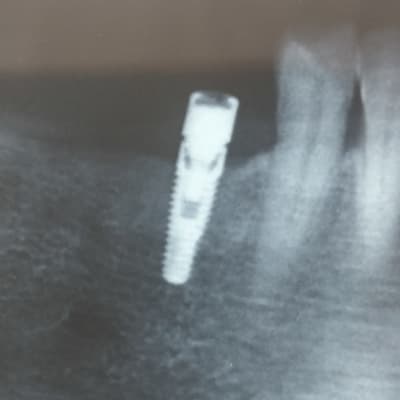

Bonjour à tous, implant posé il y a une dizaine d'années par un confrère parti à la retraite.

D'après mon prothésiste, le praticien posait du IDI et du easy implant.

désolé mais radios trop floues, j'ai trop de correspondances pour donner un résultat

J'ai celle-ci qui est plus nette, j'espère que ça peut convenir.

Je pence que c'est du keystone

https://www.spotimplant.com/fr/implants-dentaire/keystone-dental/primaconnex-tapered

pour être certain, démonter le locator (à mon avis c'est çà) et si la connexion est en 6 lobes, banco....

et la couleur de la connexion donne le diamètre de la plateforme